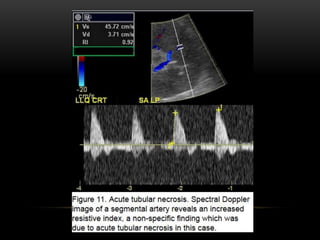

In cases of severe acute rejection,

the transplanted kidney becomes

edematous and manifests as a

globular, hypoechoic mass with poor

differentiation of the central renal

sinus fat.

The edema leads to increased

vascluar resistance and elevation

of the resistive index.

However, the finding of increased

resistive index is a non-specific

finding which can also be seen in

the setting of infection, acute

tubular necrosis, perioperative

ischemia, hydronephrosis and

extrinsic compression